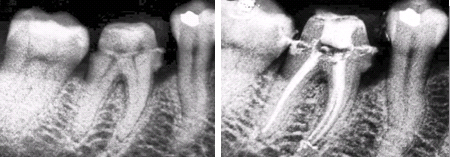

Endodontics (Root canal treatments) ![]()

The root canal is the hollow area at the center of a tooth.

Years ago, if you had a tooth with a diseased nerve, you'd probably lose that tooth. Today, with a special dental procedure called “root canal therapy” you can save that tooth. Inside each tooth is the pulp which provides nutrients and nerves to the tooth, it runs like a thread down through the root. When the pulp is diseased or injured, the pulp tissue dies. If you don't remove it, your tooth gets infected and you could lose it. After the dentist removes the pulp, the root canal is cleaned and sealed off to protect it. Then your dentist will decide if it is necessary to place a titanium endopost inside the tooth treated and a crown over the tooth to help make it stronger.

When the pulp is diseased or injured and can't repair itself, it dies. The most common cause of pulp death is a cracked tooth or a deep cavity. Both of these problems can let germs (bacteria) enter the pulp. Germs can cause an infection inside the tooth. Left without treatment, pus builds up at the root tip, in the jawbone, forming a "pus-pocket" called an abscess. An abscess can cause damage to the bone around the teeth.

When the infected pulp is not removed, pain and swelling can result. Certain byproducts of the infection can injure your jaw bones. Without treatment, your tooth may have to be removed

Root canal treatments often involves from one to three visits. During treatment, our endodontist (a dentist who specializes in problems of the pulp) removes the diseased pulp. The pulp chamber and root canal(s) of the tooth are then cleaned, filled and sealed.